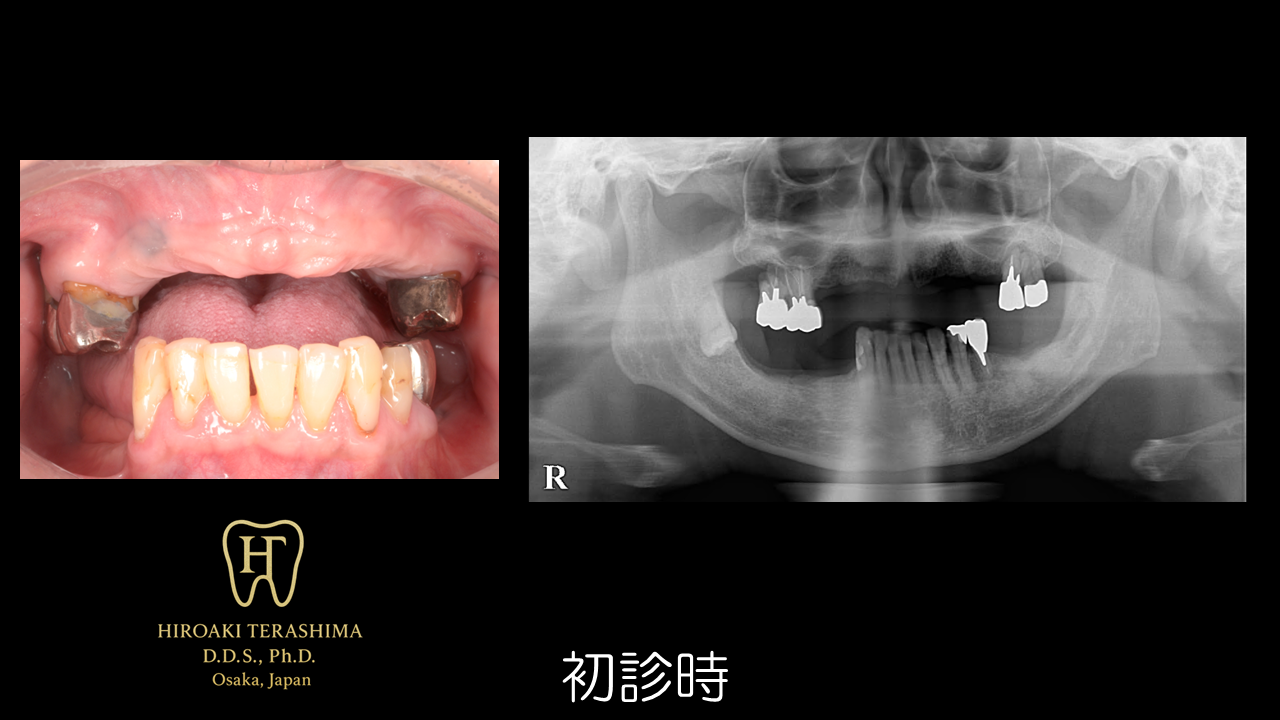

初診時の状態